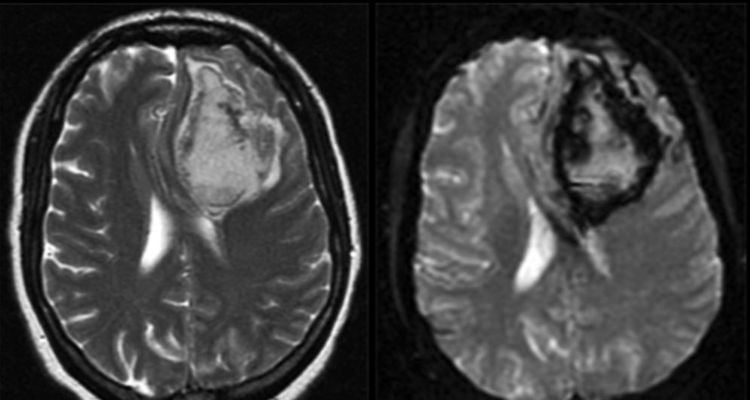

3.5 Xuất huyết não

Xuất huyết não là tình trạng chảy máu ở bên trong não bộ.

3.8 Khối u não

Khối u não bao gồm các mô phát triển bất thường bên trong não bộ. Dù là ác tính hay lành tính thì các khối u não cũng có thể gây ra các vấn đề về não bộ do áp lực mà chúng tác động lên não.